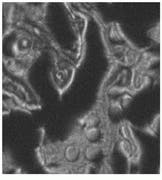

Samples were imaged containing Dacron that had migrated through the breast tissue, forming local aggregates and microstructures (see Fig. 3 and cover). Conventional optical microscopy could not unequivocally determine which of the observed structures were due to Dacron inclusions. One image in Fig. 3 is a bright-field image of the breast-tissue cross section. The other, a Raman image, was taken at 1615 cm-1, which is specific to Dacron. The presence of Dacron was confirmed by using the Raman microscope to take Raman microspectra of these structures at each of the several thousand pixels contained in the chemical image data set.

FIGURE 3. In Raman pathology studies of Dacron in human breast tissue, bright-field image taken through a microscope reveals aggregates (A), while Raman image (taken at 1615 cm-1 ) shows inclusions as bright structures (B).